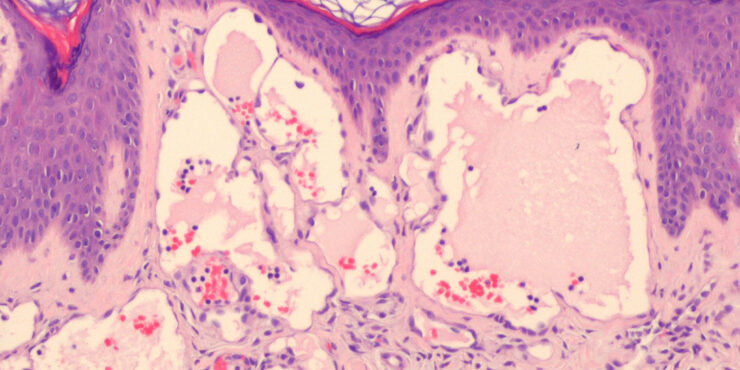

Lupus vulgaris = ุงูุฐุฃุจ ุงูุดุงุฆุน Lupus Vulgaris LV is an extremely chronic, progressive form of cutaneous tuberculosis occurring in individuals with moderate immunity and a high degree of tuberculin sensitivity. Differential Diagnosis of Tuberculosis Verrucosa Cutis ยท Warts or keratoses ยท Hyperkeratotic lupus vulgaris ยท Blastomycosis ยท Chromomycosis ยท Bromoderma ยท Lesions due to […]